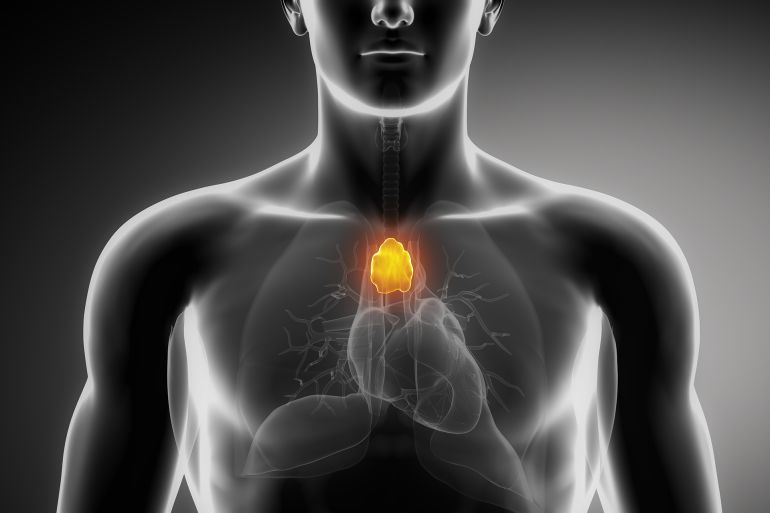

تتربع الغدة الزعترية في الجزء العلوي بين الرئتين خلف عظمة القص من القفص الصدري، وتبدأ عملها أثناء تكون الجنين في رحم أمه لتستقبل الخلايا البيضاء اللمفاوية تحديدا وتسهم في نضجها وتمايزها مكونة الخلايا التائية (T-cells)، فتستكمل جل عملها خلال مرحلة الطفولة، وهي المسؤولة بدورها عن مواجهة الفيروسات والبكتيريا والأجسام الغريبة التي تغزو الجسم لاحقا.

والغدة الزعترية أحد أجزاء الجهاز اللمفاوي، تبدأ بالضمور وتفقد جزءا كبيرا من وظائفها مع مرحلة البلوغ، فتتحول معظم أنسجتها الوظيفية لنسيج دهني غير فاعل.